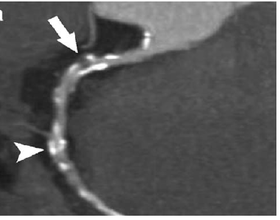

Computed tomography or heart CT scan (CT coronary angiogram) is a procedure used to assess the extent of occlusion in the coronary arteries, usually in order to diagnose coronary artery disease. The patient is injected with an intravenous dye (iodine) and then their heart is scanned using a high speed CT scanner, allowing radiologists to assess the blood flow to their heart muscle.